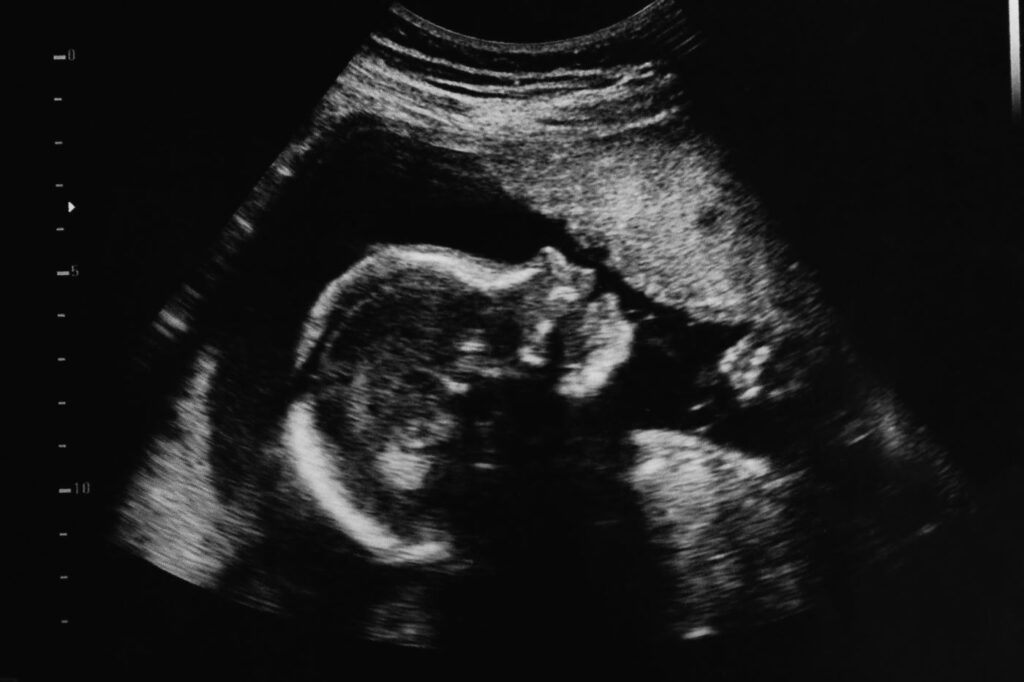

We may not be privy to Screwtape’s letters on the understanding of the meaning of the possessive pronoun “my” in “my embryo,” but judging from jurisprudential trends, we would be able to hazard a very good guess. A recent law review article in the Harvard Journal of Law & Public Policy by Anthony Jose Sirven does us a favor by doing just that.

Sirven notices that courts across the country have classified embryos not as persons, but as property of their progenitors—and as such, contract, property, and marital property laws apply to them. Thus Sirven observes that in one case, the Colorado Supreme Court understood the embryos of a couple seeking a divorce to be lacking the “status of ‘person,’” and to be their marital property instead. Thus, “an enforceable agreement between the parties regarding the[ir] disposition” would apply to the embryos. Should no agreement exist, the state’s equitable distribution laws would apply.

Sign up and get our daily essays sent straight to your inbox.In another case, a Texas appellate court bifurcated the class of two types of embryos: in vivo and in vitro. Embryos in vivo enjoyed the protection of a Texas post-Dobbs personhood statute—but not so much the same kind of human embryos who happen to be in a different location, that is, in vitro. The divorcing couple in that case, with embryos from IVF, saw the court enforce their earlier IVF agreement (which had given the embryos to the husband), rather than recognize that the embryos in the deep freezer enjoy the protection of the personhood statute as their brethren in the womb would.

By one estimate, only 7 percent of IVF embryos make it to live birth. Many of the rest are indefinitely in limbo in the freezer or else sent to their destruction.

Or is the embryo instead a person? After all, courts that don’t pay any attention to the father’s due-process property rights, Sirven points out, would imply, or might even simply hold, that the embryo is not properly understood as property. They might hold that people could not have ownership interest over embryos as a class, thus rendering any contracts over embryos, such as IVF or surrogacy contracts, unenforceable. As Sirven posits, it’s really not because embryos are living creatures that we have a hangup over this issue, is it? We have no qualms with calling our horses, sheep, cattle, and dog our chattel and thus our property. It’s because human embryos are human, and uniquely so, that we do.

Robert P. George has written that human embryos are embryonic humans. So it is that the reader of these pages and I both, as the persons that we are now, have in fact been the same persons—indeed the very same living bodily entities—ever since we were tiny embryos in our mothers’ wombs, each of us “a unified, self-integrating human organism.” But if that’s the case, and if the reader’s life and mine are protected by the law, should not embryos as persons enjoy the same protection? The Fourteenth Amendment guarantees the fundamental rights of persons, the foremost of which is life. John Finnis and Robert P. George have argued that the unborn are constitutional persons, and thus entitled to this very Fourteenth Amendment protection. Would that this be the law of the land, and soon.